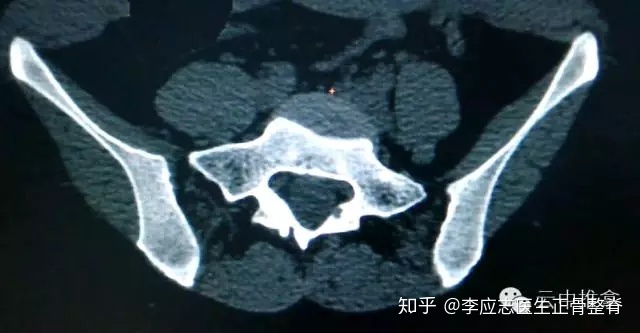

CT扫描有时可以显示关节表面和周围骨骼的更多细节。如果x光显示可能有什么东西影响了SI关节,你的医生可能会建议进行CT扫描以获得更好的观察。

CT扫描可以看出两侧骶髂关节不对称

CT三维重建可以看出骨盆的骨性结构变化,上图就是明显的不对称。